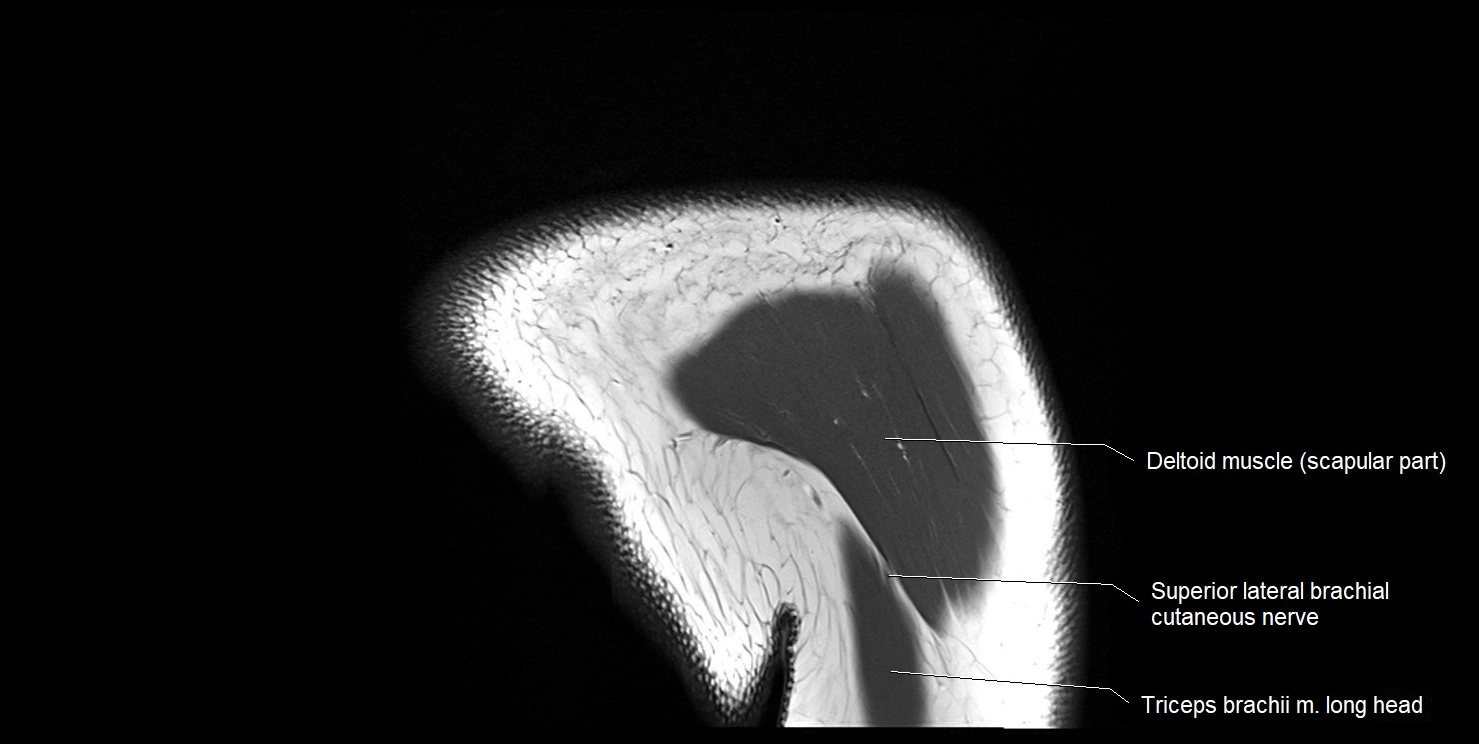

CT image

image